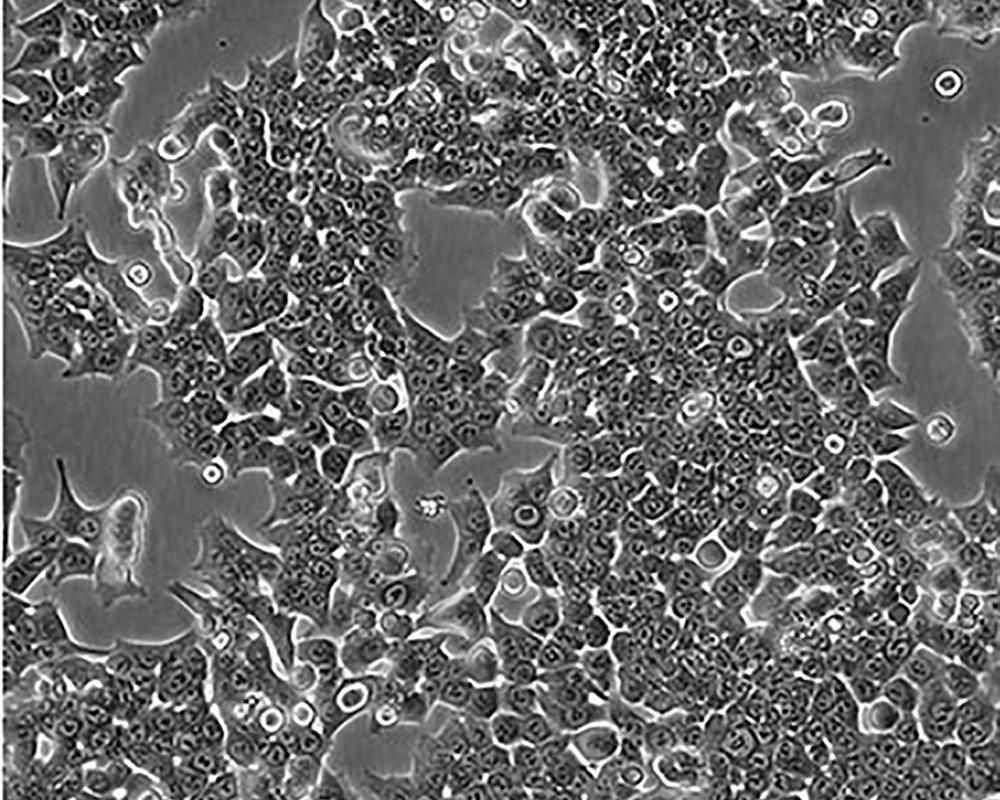

HCT 116

產品名稱 HCT 116

中文名稱 人結直腸腺癌細胞

組織來源 結腸腺癌;男性

生長特性 adherent

形態特征 epithelial

細胞描述 The cells are positive for keratin by immunoperoxidase staining.HCT 116 cells are positive for transforming growth factor beta 1(TGF beta 1) and beta 2(TGF beta 2) expression.